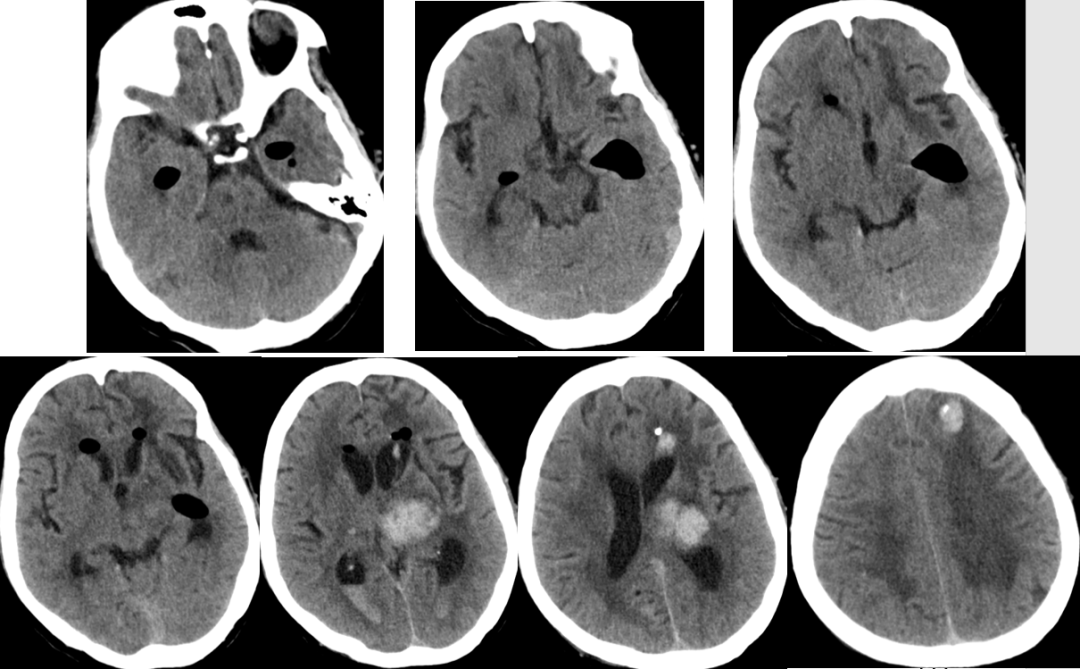

2014-11-18 0am CT

2014-11-18 10am CT

2014-11-19 CT

2014-11-20 CT

2014-11-24 CT

2014-11-18 CT

2014-11-27 CT

2014-12-2 CT